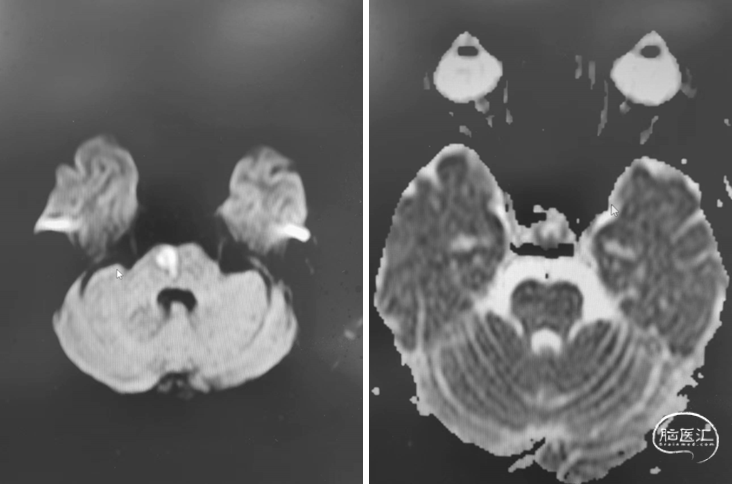

首次发病:

DWI

MRA

重要影像结论:后循环供血区多发梗死灶,后循环血管显影不良。